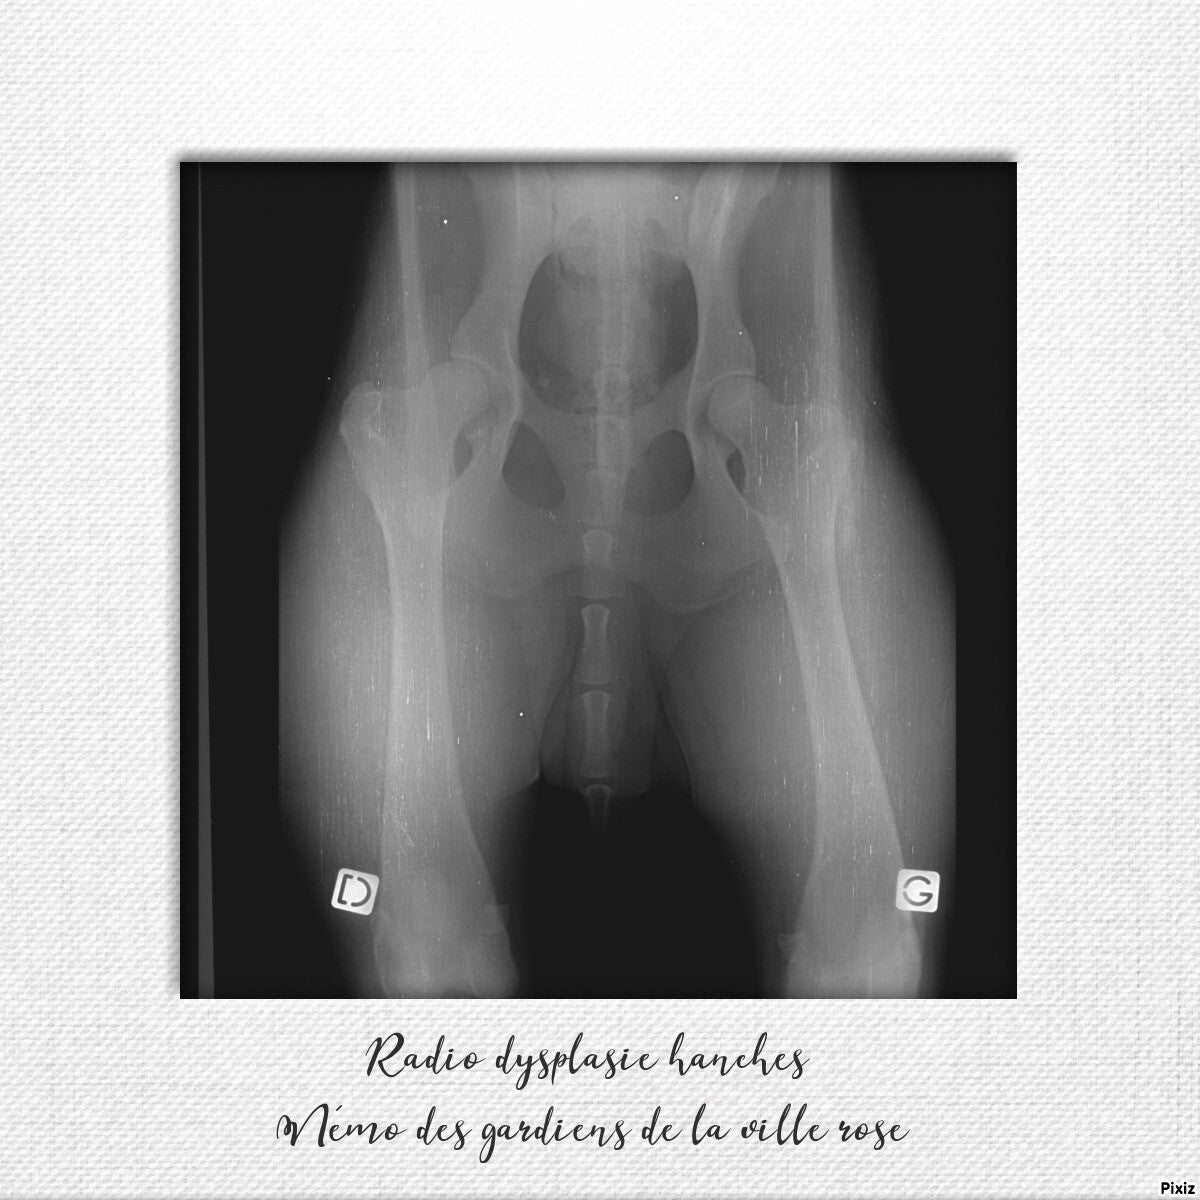

Némo des Gardiens de la ville rose né à l'élevage le 8 Juillet 2017.

Indemne de dysplasie .

Dysplasie hanches OK .